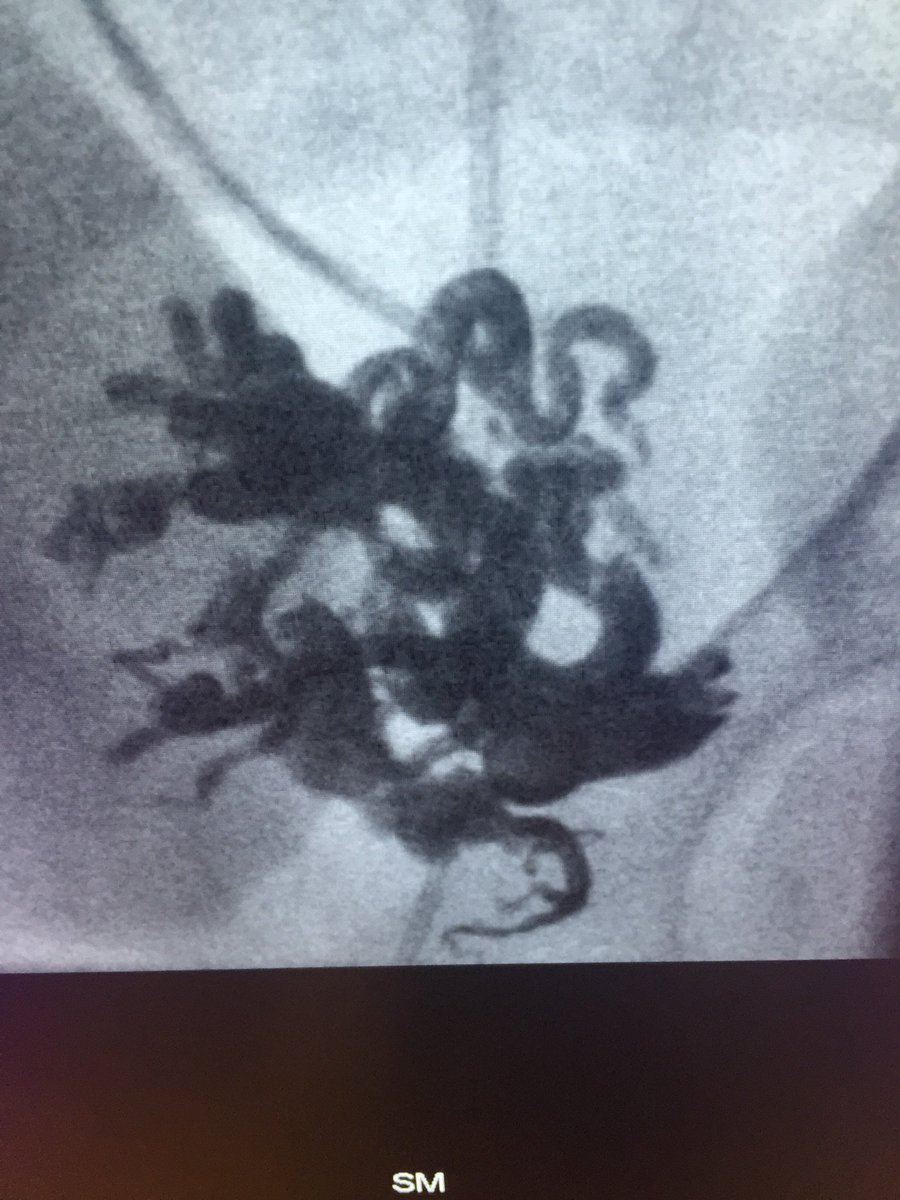

Renal AVM causing a varicocele and Dyspnea- embo X 2 1. AVM-AVP &coils 2. varicocele- STS&AVP -dyspnea resolved on the table #irad SIR RFS

Renal AVM causing a varicocele and Dyspnea- embo X 2

1. AVM-AVP &coils

2. varicocele- STS&AVP

-dyspnea resolved on the table #irad <a href="/SIRRFS/">SIR RFS</a>